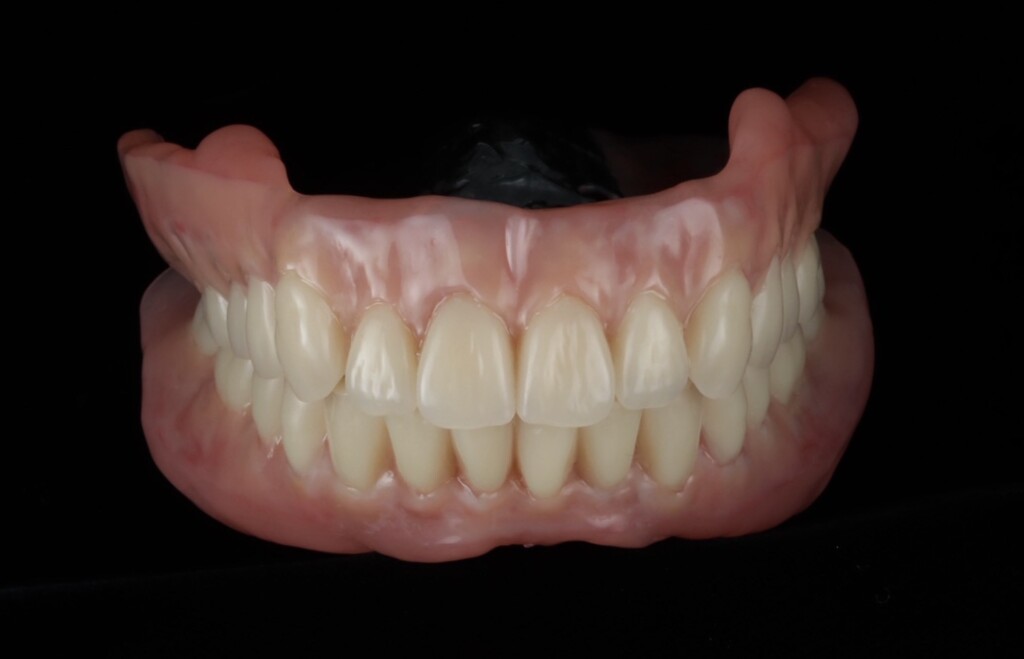

最終精密義歯

歯肉の質感まで再現された最終精密義歯

天然歯と見分けがつかない最終精密義歯